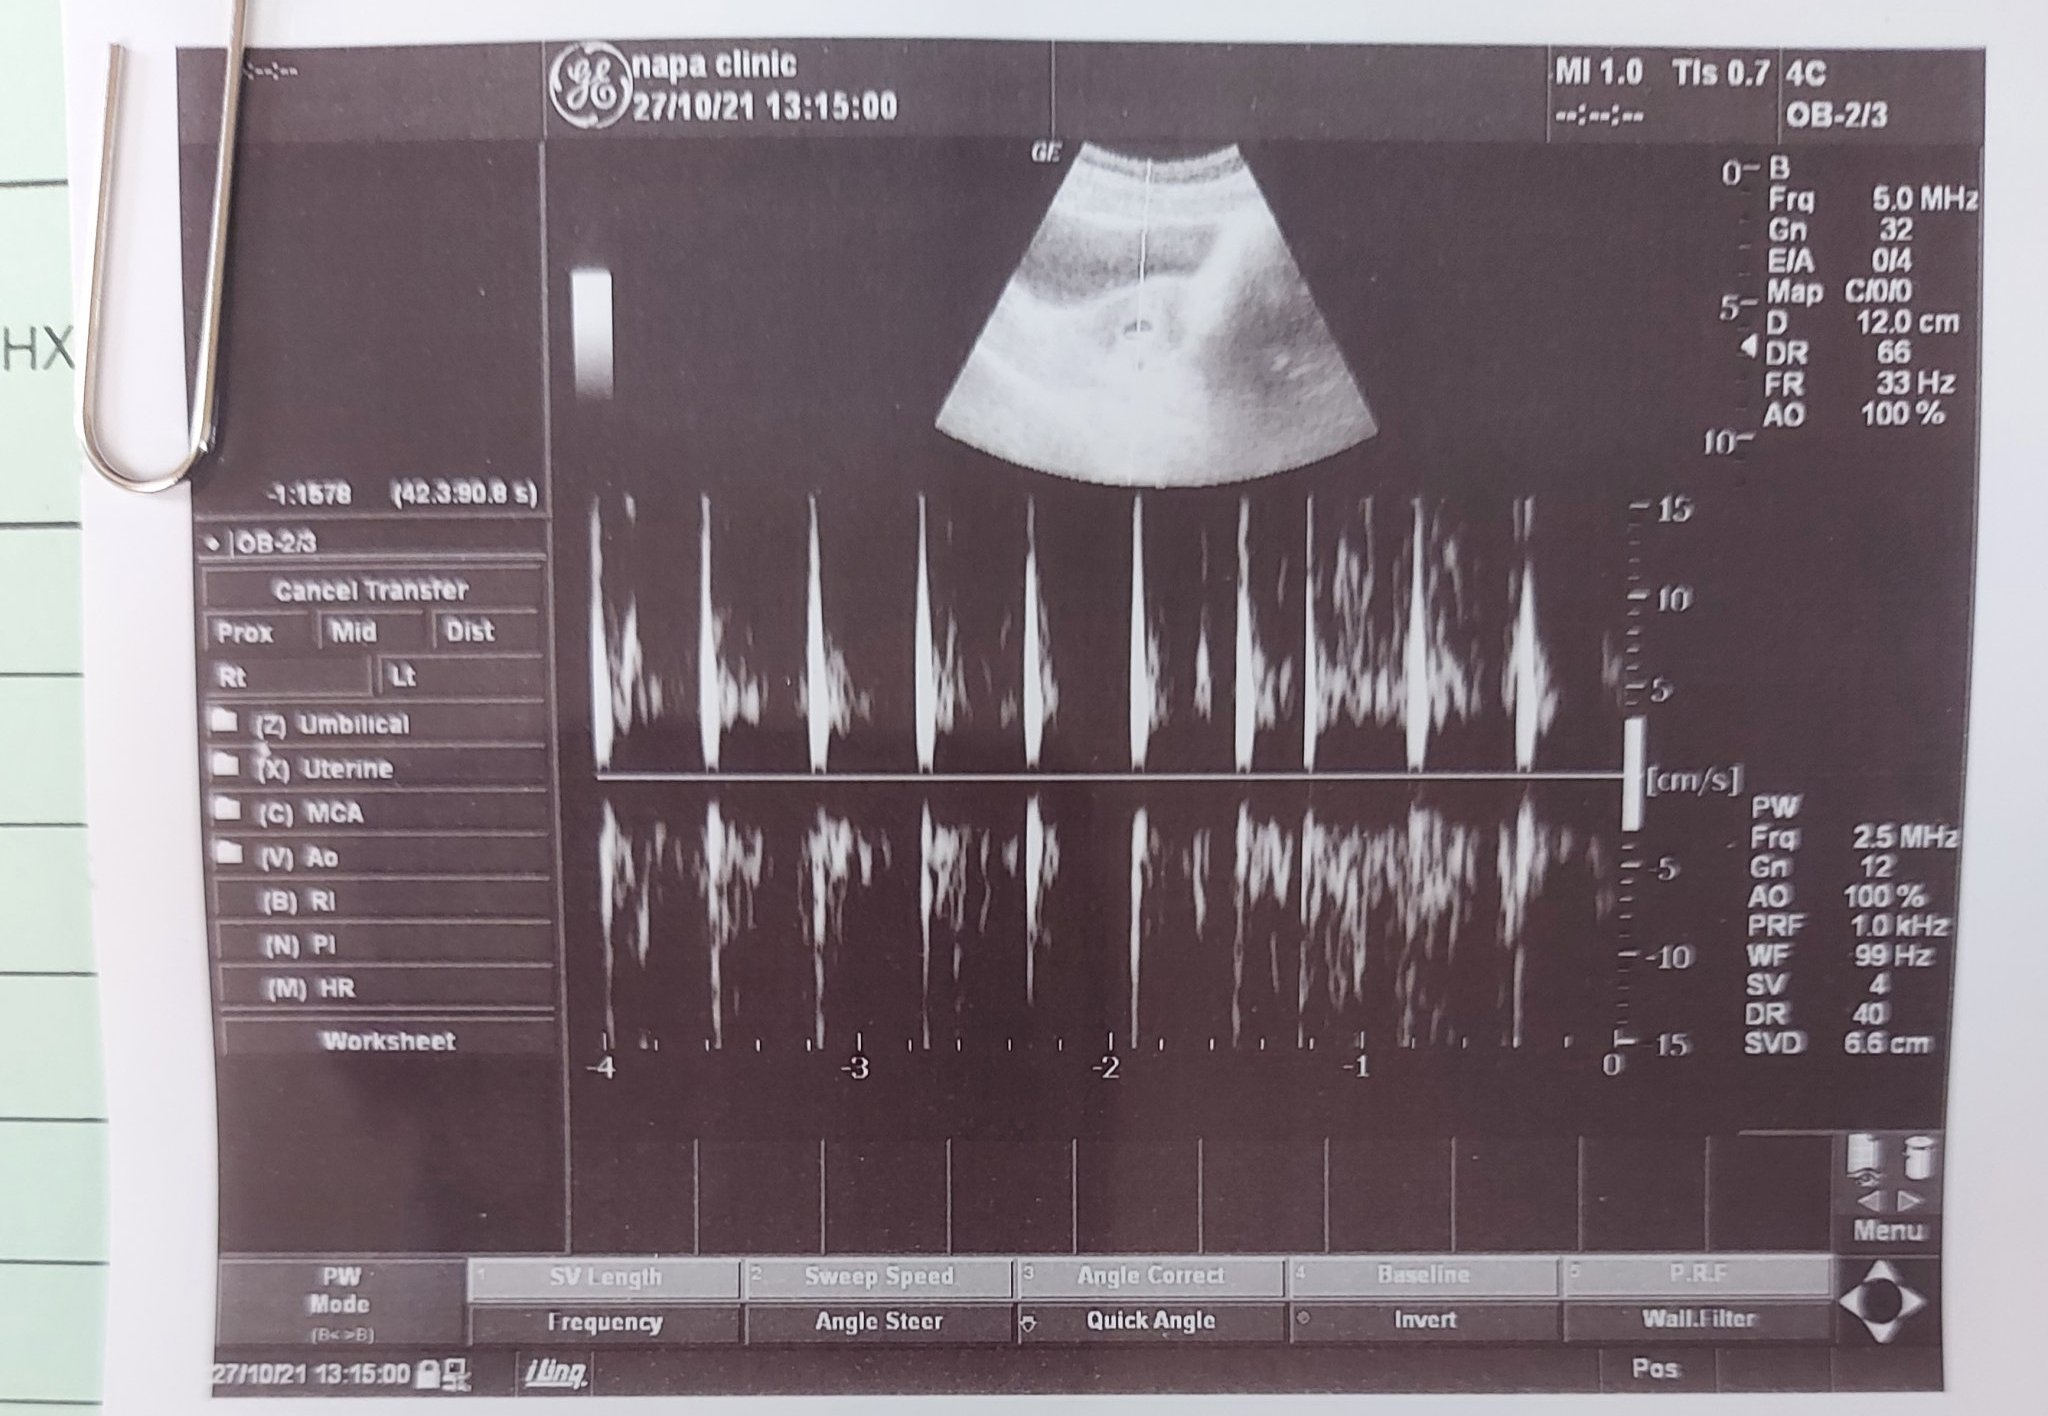

Може ли малко помощ тябва да съм 7г.с.и 5 дни а док каза че отговаря на 6г.с. ако рзбирате от снимки дали пише нещо